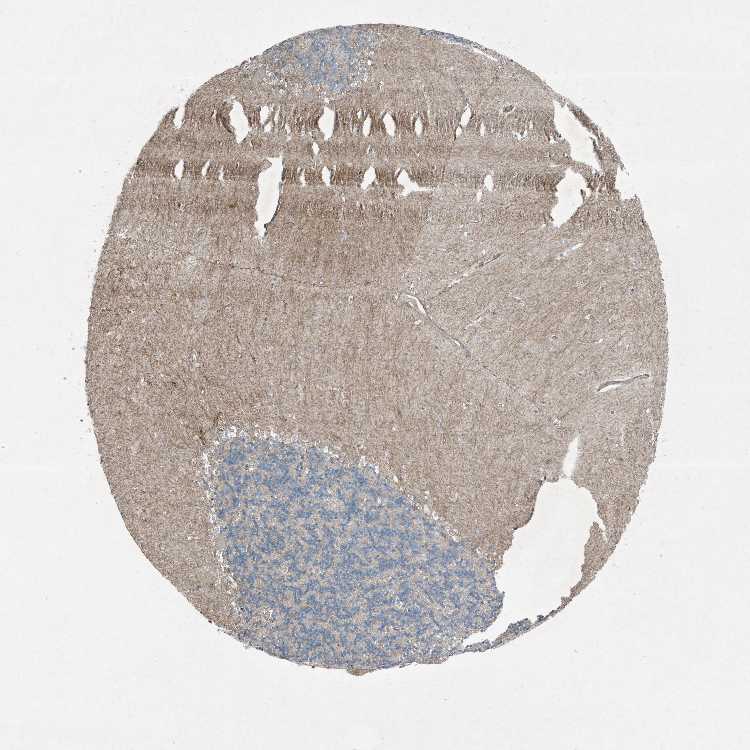

CEREBELLUM - Antibody stainingi

Antibody staining in the annotated cell types in the current human tissue is reported as not detected, low, medium, or high, based on conventional immunohistochemistry profiling in selected tissues. This score is based on the combination of the staining intensity and fraction of stained cells.

Each image is clickable and will lead to virtual microscopy that enables deeper exploration of all samples and also displays staining intensity scores, fraction scores and subcellular localization as well as patient and tissue information for each sample.

Antibody HPA046074Antibody CAB033822

Purkinje cells Not detectedNot detected

Cells in granular layer Not detectedNot detected

Cells in molecular layer Not detectedNot detected